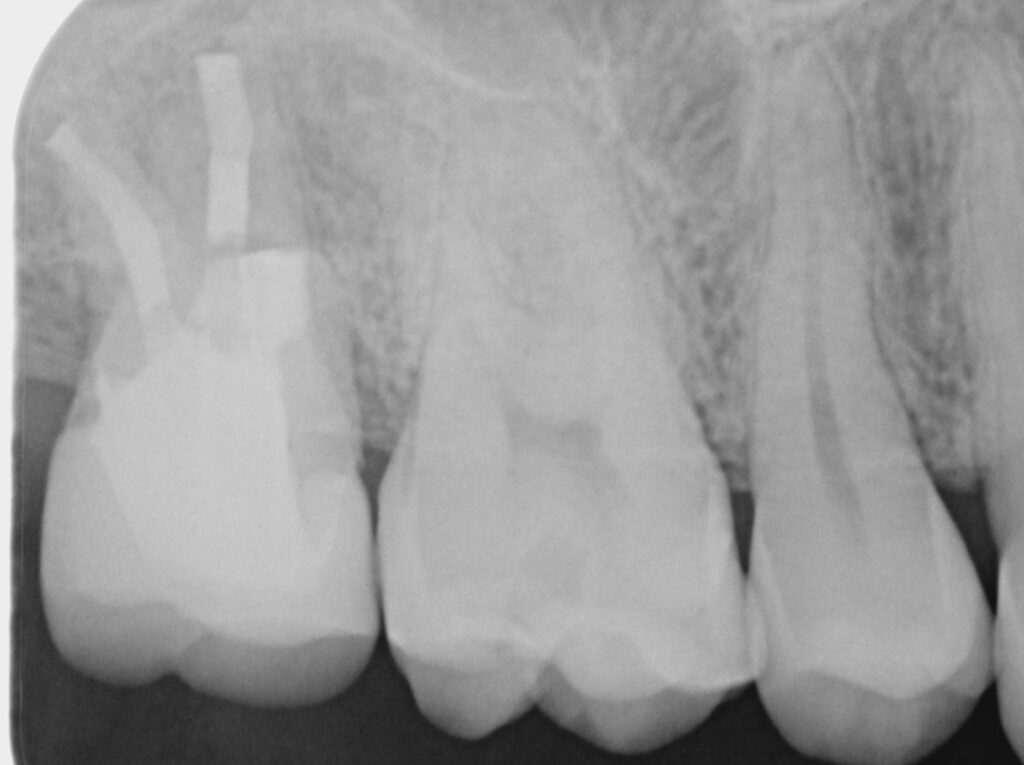

■ 術後経過

術後の経過観察において、

レントゲンおよびCTにて術前と比較を行いました。

その結果、

- 根尖部の透過像は縮小し

- 骨の再生が認められました

また臨床的にも、

- 咬合時の違和感は消失

- 日常生活での不快症状も認められない状態

となり、良好に経過しています。